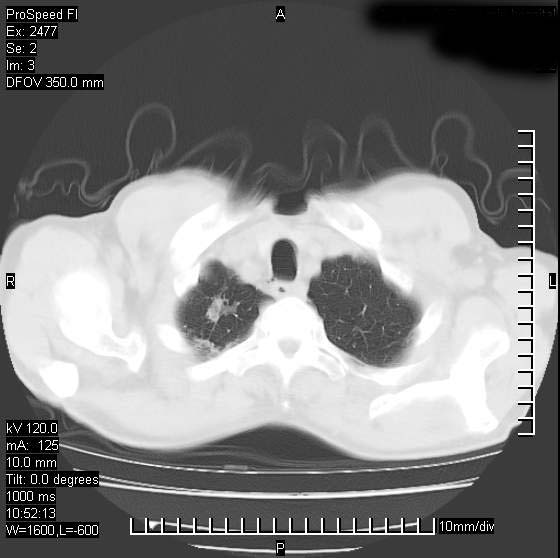

以下是引用天南地北在2007-10-9 14:29:00的发言:[br]1:右上肺结核[br]2:右肺下叶肿块:不支持肺癌,首先考虑炎性病变-肺脓疡可能性大[br]理由:1:临床病史支持,肺脓肿症状不明显应该是不规则服药造成。[br] 2:肿块边缘模糊,周围可见炎性渗出,长毛刺,内见支气管征,不过有点不规则。[br] 我感觉下肺癌这个诊断有点偏左,建议积极抗炎治疗后复查

以下是引用卜一在2007-10-9 15:55:00的发言:[br][br] [br] 1:右上肺结核[br]2:右肺下叶肿块:不支持肺癌,首先考虑炎性病变-肺脓疡可能性大[br]理由:1:临床病史支持,肺脓肿症状不明显应该是不规则服药造成。[br] 2:肿块边缘模糊,周围可见炎性渗出,长毛刺,内见空气支气管征,不过有点不规则。[br] 我感觉下肺癌这个诊断有点偏左,建议积极抗炎治疗后复查![br]支持! [br] [br] [br]

以下是引用wxy7406在2007-10-9 21:02:00的发言:[br]结合临床病史首先考虑感染性病变,但周围型肺癌不能除外,1.患者年龄偏大2.临床有咯血3.(也觉得是最重要的一点)病灶内有偏心性空洞。

以下是引用王仕学在2007-10-9 13:48:00的发言:[br]右下肺周围性肺癌可能性大,最好活检吧

以下是引用hhcckk在2007-10-9 15:18:00的发言:[br]右上肺病灶考虑结核,病灶多种形态并存(纤维化、增殖性病灶并存)[br]右下肺病灶比较难说,个人意见更趋向于“天南地北”的诊断----肺脓肿[br]1、病人有明显的寒战,高热,肿瘤病人很少出现[br]2、病灶周围的肺纹理走向柔和,没有肿瘤病灶常见的集束征[br]3、病灶边缘的毛刺较长,恶性肿瘤多为短毛刺[br]痰中血丝和病人的年龄是两个不利于良性肿块的因素,建议早点活检

以下是引用ydx_74在2007-10-9 15:53:00的发言:[br]右上肺结核,右下中心性肺癌可能大,肺门淋巴结肿大。